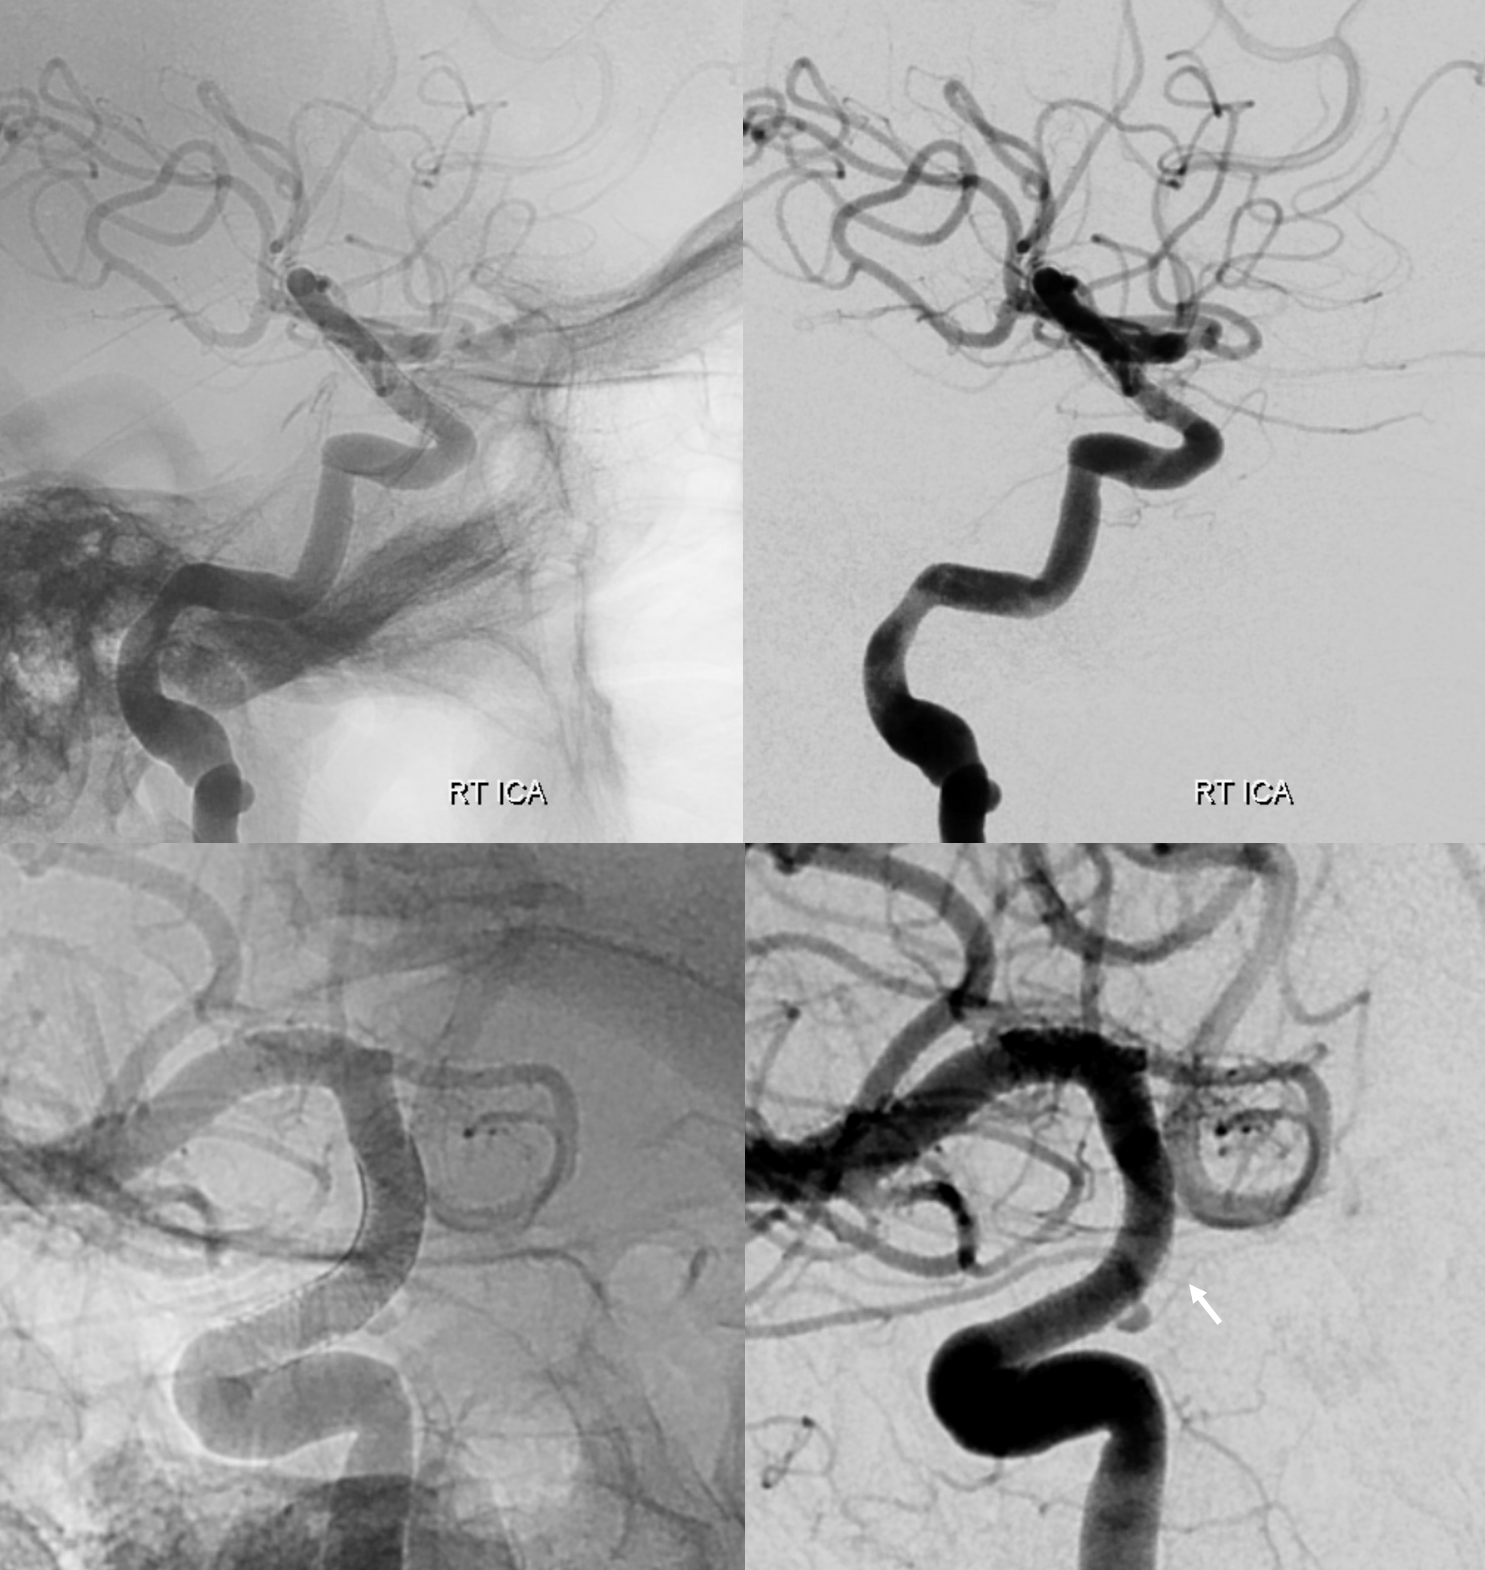

DSA — yes, they do exist on DSA also. A slight contralateral oblique is probably best — to throw them off other vessels. Here, an LAO of right ICA injection shows a farily promenent superior hypophyseal (white arrow, with an infundibulum), supplying the pituitary stalk (black arrwos). Also seen is inferior hypophyseal (dashed white arrow) supply of the posterior pituitary (dashed black arrow)

Case courtesy Dr. Eytan Raz — here is a beautiful example of a very dominant superior hypophyseal artery (arrow) supplying the posterior hypophysis (arrowhead), with a correspondingly small inferior hypophyseal contribution from the MHT (dashed arrow)

Cross eye stereo

View from the back — again small inferior hypophyseal, big superior hypophyseal — balance again… See the beautiful vascular ring of the posterior pituitary — the connecting it with the contralateral side